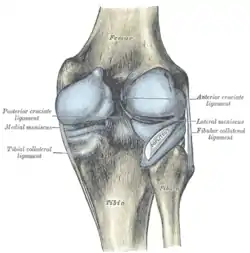

Ligaments

The ligaments surrounding the knee joint offer stability by limiting movements and, together with the menisci and several bursae, protect the articular capsule.[16]

Intracapsular

The knee is stabilized by a pair of cruciate ligaments. These ligaments are both extrasynovial, intracapsular ligaments.[17] The anterior cruciate ligament (ACL) stretches from the lateral condyle of femur to the anterior intercondylar area.[13] The ACL is critically important because it prevents the tibia from being pushed too far anterior relative to the femur.[13] It is often torn during twisting or bending of the knee.[18] The posterior cruciate ligament (PCL) stretches from medial condyle of femur to the posterior intercondylar area. This ligament prevents posterior displacement of the tibia relative to the femur.[13] Injury to this ligament is uncommon but can occur as a direct result of forced trauma to the ligament.

The transverse ligament stretches from the lateral meniscus to the medial meniscus. It passes in front of the menisci. It is divided into several strips in 10% of cases.[10]: 208 The two menisci are attached to each other anteriorly by the ligament.[19] The posterior (of Wrisberg) and anterior meniscofemoral ligaments (of Humphrey) stretch from the posterior horn of the lateral meniscus to the medial femoral condyle. They pass anterior and posterior to the posterior cruciate ligament respectively.[13][10]: 208 The meniscotibial ligaments (or "coronary") stretches from inferior edges of the menisci to the periphery of the tibial plateaus.

Extracapsular

The patellar ligament connects the patella to the tuberosity of the tibia. It is also occasionally called the patellar tendon because there is no definite separation between the quadriceps tendon (which surrounds the patella) and the area connecting the patella to the tibia.[20] This very strong ligament helps give the patella its mechanical leverage [21] and also functions as a cap for the condyles of the femur. Laterally and medially to the patellar ligament, the lateral and medial retinacula connect fibers from the vasti lateralis and medialis muscles to the tibia. Some fibers from the iliotibial tract radiate into the lateral retinaculum and the medial retinaculum receives some transverse fibers arising on the medial femoral epicondyle.[10]: 206

The medial collateral ligament (MCL a.k.a. "tibial") stretches from the medial epicondyle of the femur to the medial tibial condyle. It is composed of three groups of fibers, one stretching between the two bones, and two fused with the medial meniscus. The MCL is partly covered by the pes anserinus and the tendon of the semimembranosus passes under it.[10]: 206 It protects the medial side of the knee from being bent open by a stress applied to the lateral side of the knee (a valgus force).[10]: 206

The lateral collateral ligament (LCL a.k.a. "fibular") stretches from the lateral epicondyle of the femur to the head of fibula. It is separate from both the joint capsule and the lateral meniscus.[10]: 206 It protects the lateral side from an inside bending force (a varus force). The anterolateral ligament (ALL) is situated in front of the LCL.

Lastly, there are two ligaments on the dorsal side of the knee. The oblique popliteal ligament is a radiation of the tendon of the semimembranosus on the medial side, from where it is direct laterally and proximally. The arcuate popliteal ligament originates on the apex of the head of the fibula to stretch proximally, crosses the tendon of the popliteus muscle, and passes into the capsule.[10]: 206

Illustrations

- Cruciate ligaments

- Left knee-joint from behind, showing interior ligaments.

- Capsule of right knee-joint (distended). Lateral aspect.

- Anterior and lateral view of knee.

- Anterior view of knee.